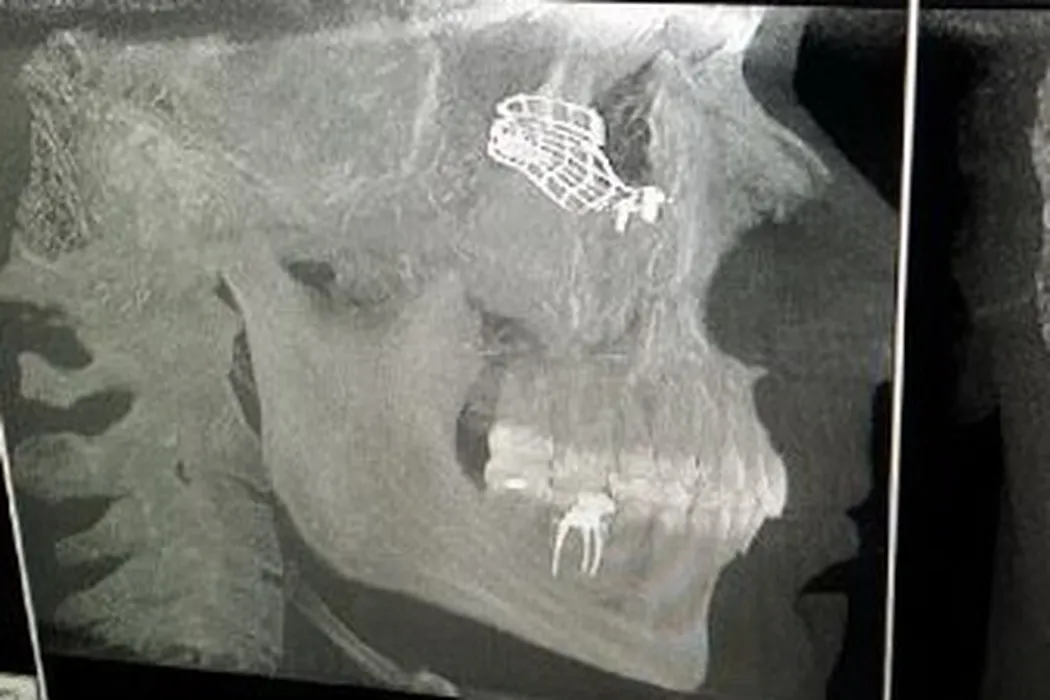

Rusescu: „Sunt șocat, nu e normal să fie tolerate astfel de acte! Încă nu pot să estimez data când voi redeveni om normal”. Steaua a publicat fotografiile cu zona afectată